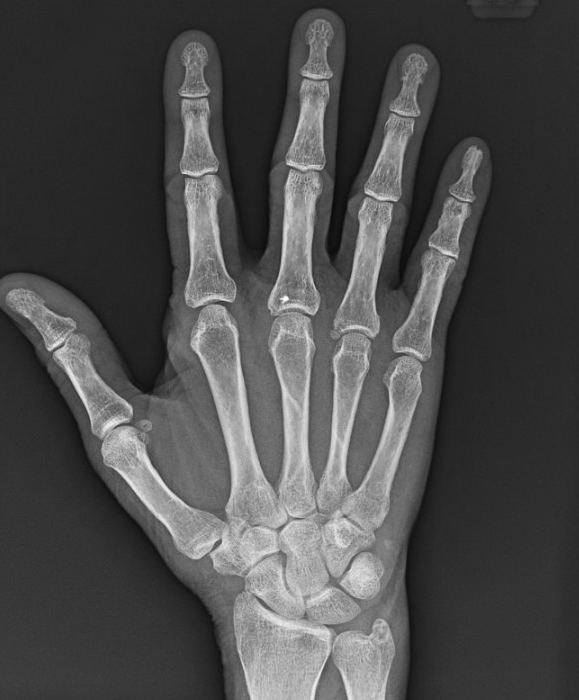

These are “non-displaced” fractures of the third and fourth metacarpals - the long bones of your hand.